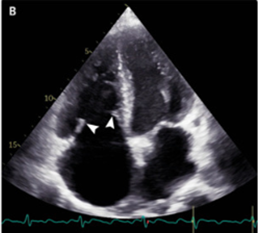

経胸壁心エコー検査では、可動性が制限され肥厚した硬い三尖弁と重度の三尖弁逆流が示唆された。

肺動脈弁ははっきりと観察されなかったが、肺動脈逆流も示唆された。